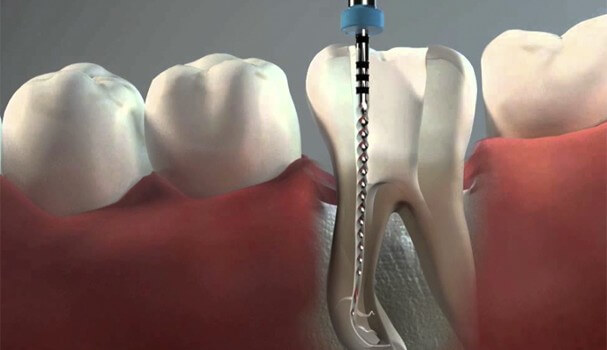

Nuestra prioridad es mantener siempre todos los dientes. Cuando no es posible, hay que hacer la extracción y posterior sustitución del diente; pero hay que tener en cuenta que ninguna

La extracción de las muelas del juicio es la intervención más frecuente en Cirugía Bucal.

Ante la presencia de un cordal (muela del juicio) podemos optar por diferentes conductas: